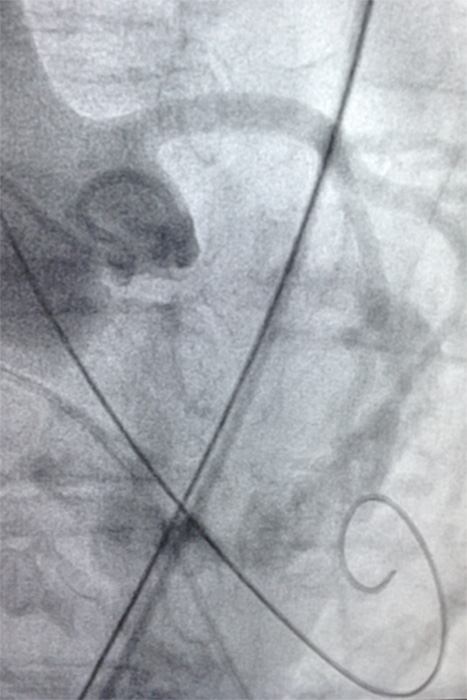

Symedrix has developed the INNOWI® and INNOWI SX® pre-shaped guide wires specifically to improve TAVI procedures.

The INNOWI® wires have three independent zones of stiffness providing optimal support. The ultra-stiff proximal portion of the wires facilitates easy advancing of the introducer sheath and superior pushability and maneuverability. INNOWI‘s extra-stiff, respectively INNOWI SX‘s superstiff distal portion adapts perfectly to the anatomy in the aortic arch and provides sufficient guidance and support for the valve introducer system. The Pig-Tail-Tip allows atraumatic positioning in the ventricle, thereby protecting the heart muscle during the implantation of the valve.

A PTFE-coated, stainless steel wire is the key to providing maximum support and low surface friction during complex procedures.

The smooth transition from the stiff wire to the flexible tip facilitates atraumatic vessel navigation.